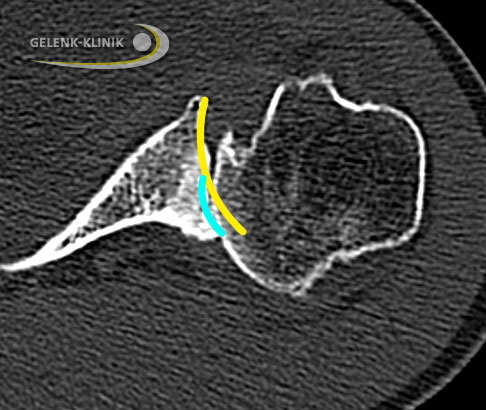

Bestehen Knochendefekte, wie sie bei einem langen Verlauf der Schulterarthrose vor allem im hinteren Bereich der Pfanne (Glenoid) auftreten können, ergänzt der Schulterspezialist die Diagnostik durch eine Computertomographie (CT). Die CT-Technik ermöglicht dem Arzt bei große Knochendefekten eine 3-D-Planung zur optimalen Vorbereitung, wenn er eine Operation in Betracht zieht.

Computertomographie: Wie ist der Knochen beschaffen?

Die Computertomographie (CT) gibt dem Orthopäden Auskunft über die Knochenqualität. Die Qualität der Knochensubstanz ist besonders wichtig, wenn der Arzt die Verankerung von Implantaten zur Behandlung der Omarthrose plant. Vor allem bei älteren Patienten mit einer bereits eingetretenen Cuff-Arthropathie ist die CT-Untersuchung wichtig, um die Knochensubstanz des Gelenkpfanne (Glenoid) zu bewerten.